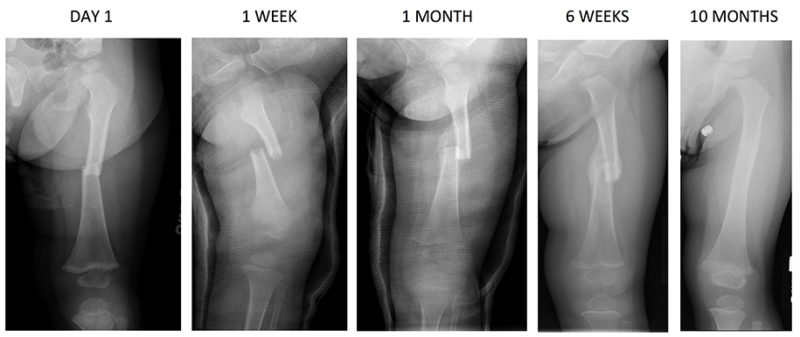

272. MAINTENANCE: Body mechanics slideshow

• 272. MAINTENANCE: Body mechanics slideshow August 26, 2025